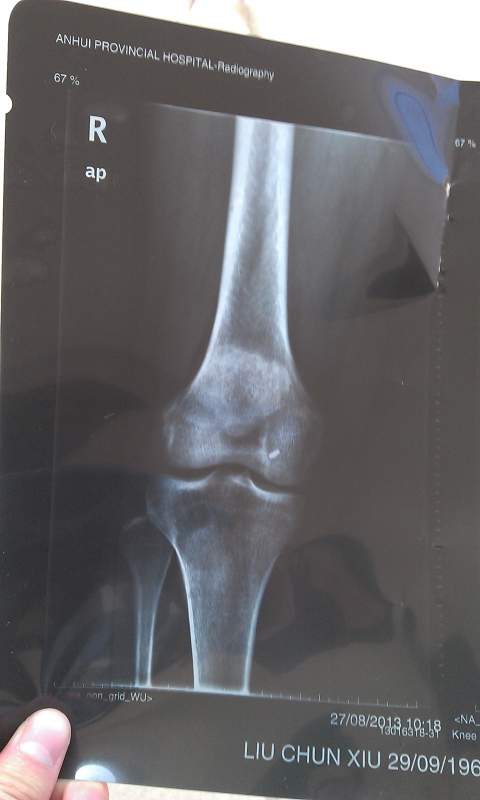

病情描述:膝盖内侧局部区域疼痛,只有那一小块地方,由于不小心崴的一下,已经有近两年时间,求助大神帮忙看下这个X光片,是个什么情况?X光片上规则白点是什么原因?是引起病症的直接原因吗? IMAG0062.jpg IMAG0063.jpg IMAG0064.jpg IMAG0065.jpg |